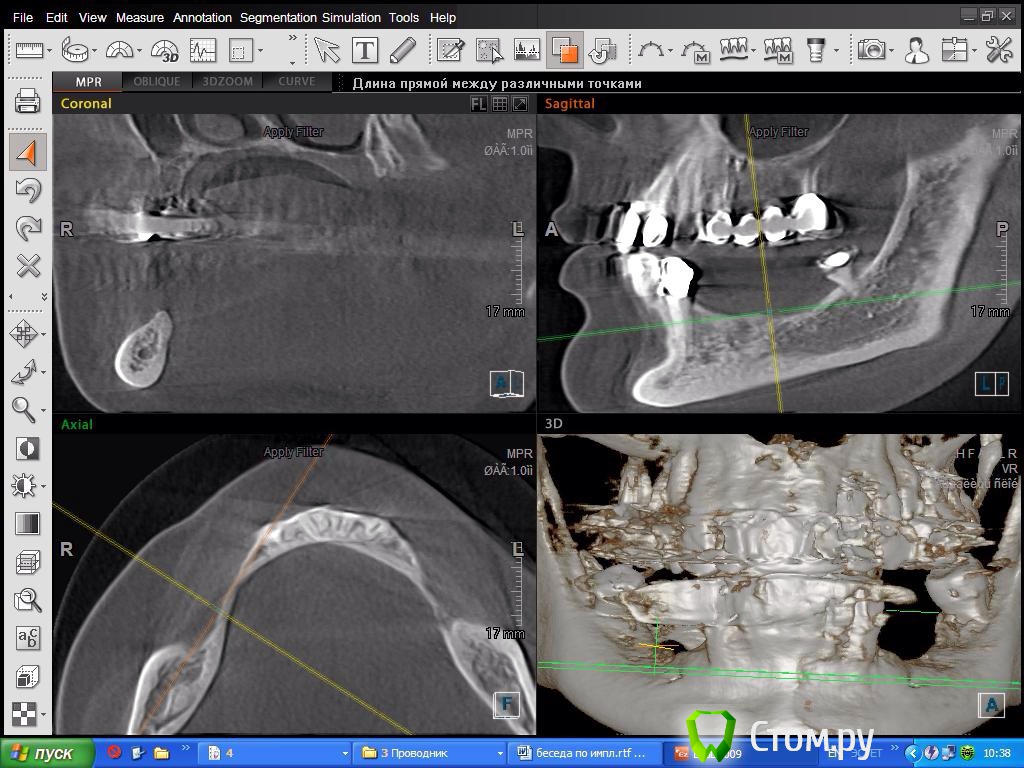

SDC Опубликовано 8 октября, 2014 Поделиться Опубликовано 8 октября, 2014 Склоняюсь в 4 кв делать консоль! Спасибо за мнениеПосмотрим срезы на уровне 2 премоляра? Получится ли имплантировать в этом месте? Ссылка на комментарий

DoktorDre Опубликовано 8 октября, 2014 Автор Поделиться Опубликовано 8 октября, 2014 Посмотрим срезы на уровне 2 премоляра? Получится ли имплантировать в этом месте?Получится, после ламинатов) Ссылка на комментарий